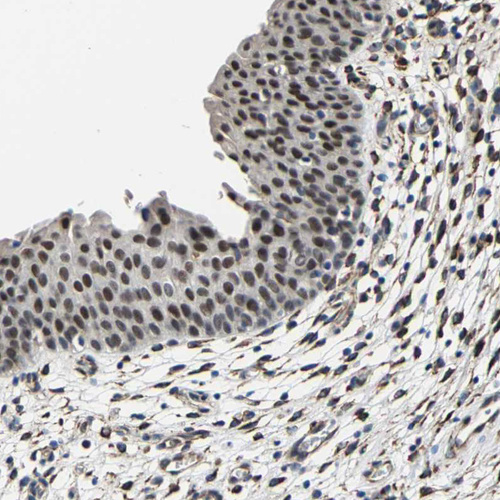

Immunohistochemical staining of human urinary bladder shows strong nuclear positivity in urothelial cells.